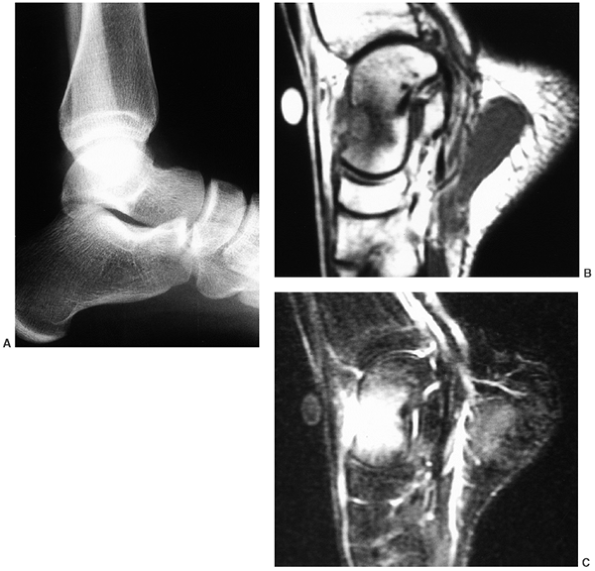

Figure 14.4 A:

Plain radiograph, lateral view, of an 18-year-old woman’s ankle. She complained of severe pain for 6 months, which was totally relieved by aspirin. There is a small erosion in the anterior neck of her talus. (Her computed tomography scan is seen in Fig. 14.3.) B: The sagittal view of a T1-weighted magnetic resonance image shows the lesion in her anterior talus. C: The T2-weighted magnetic resonance image reveals the extensive edema that is characteristic of osteoid osteoma. |

them are found in the femur or the tibia. The other half are

distributed throughout the rest of the skeleton (Fig. 14.4). The proximal femur is a common site. It is also